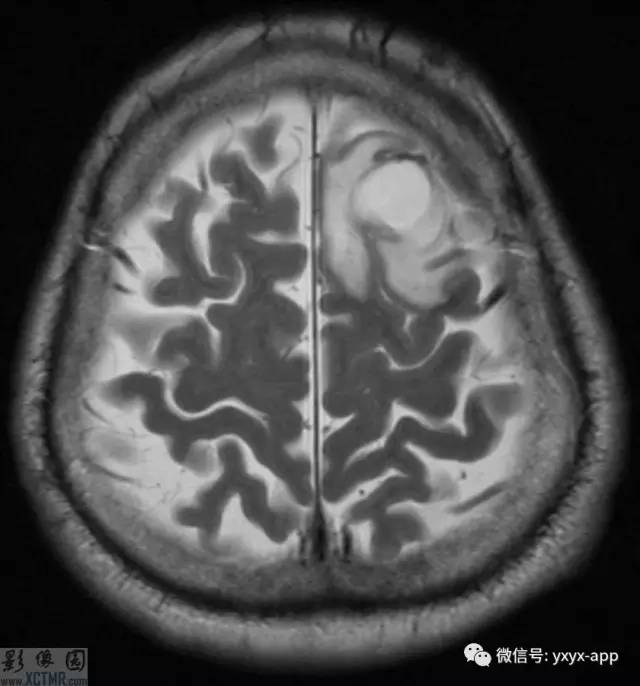

CT:左侧额叶一囊性肿块伴水肿。MRI:轴位T1WI和T2WI显示左侧额叶一囊性肿块伴周围脑实质显著水肿,但无明显占位效应。T1WI增强图显示病变为分叶环形囊状肿块伴周围脑实质水肿,囊壁环形强化,囊内及周围水肿区无强化。

影像学表现取决于感染的位置以及感染的阶段。此病例在胶状水泡阶段,寄生虫的死亡引起明显的炎性反应。影像学表现包括:围绕囊性病变的血管源性水肿;增强后环状增强;T1WI胶状囊性病变周围为低信号;有时可见T1WI头节高信号影。

MRI可以准确地显示各型的发病特点(数目、大小及部位等)。病理演变分期:依据脑囊虫的病理演变过程,将其分为囊泡期、胶样囊泡期、结节期及钙化期,各期由于所含成份的变化,而具有特征性的MRI表现。部分囊泡型及脑炎型脑囊虫病在增强扫描时可呈环形强化,脑炎型脑囊虫病通常为单发环形强化,环一般位于脑皮质内,通常为小环样强化,环壁可厚而光整,但也可厚薄不均匀,环周围常有明显的水肿。这种环形强化病灶与小脓肿环形强化很难区别,需要结合平扫表现和临床。有时环形强化内可见囊虫头节,表现为环形强化内有点状高密度和高信号,使囊虫环形强化的特征性表现,但需要与结核环形强化区别,小囊泡型囊虫病常呈多发环形强化,根据平扫表现,通常容易诊断脑囊虫病。